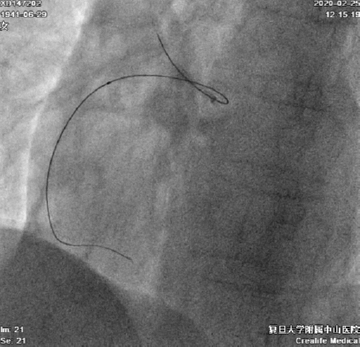

导丝通过后,Corsair微导管无法通过,在球囊辅助下尝试送入6F Guidezilla II,尝试球囊扩张右冠近段、锚定,均无法送入Guidezilla II(图6)

图6

换用4F Transporta GE成功送至右冠中段(图7)

图7